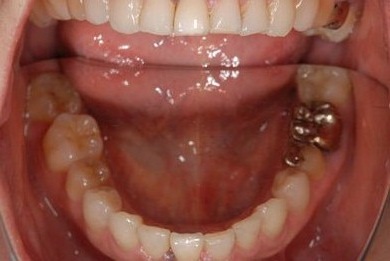

主訴 歯の差し歯が少しぐらつく。歯ぐきが違和感を感じる。

治療方針 抜歯と同時にインプラントを埋入し、治療期間を短縮する。

治療内容 インプラント1本(抜歯即日スピードインプラント)、メタルボンドセラミック1本

治療前